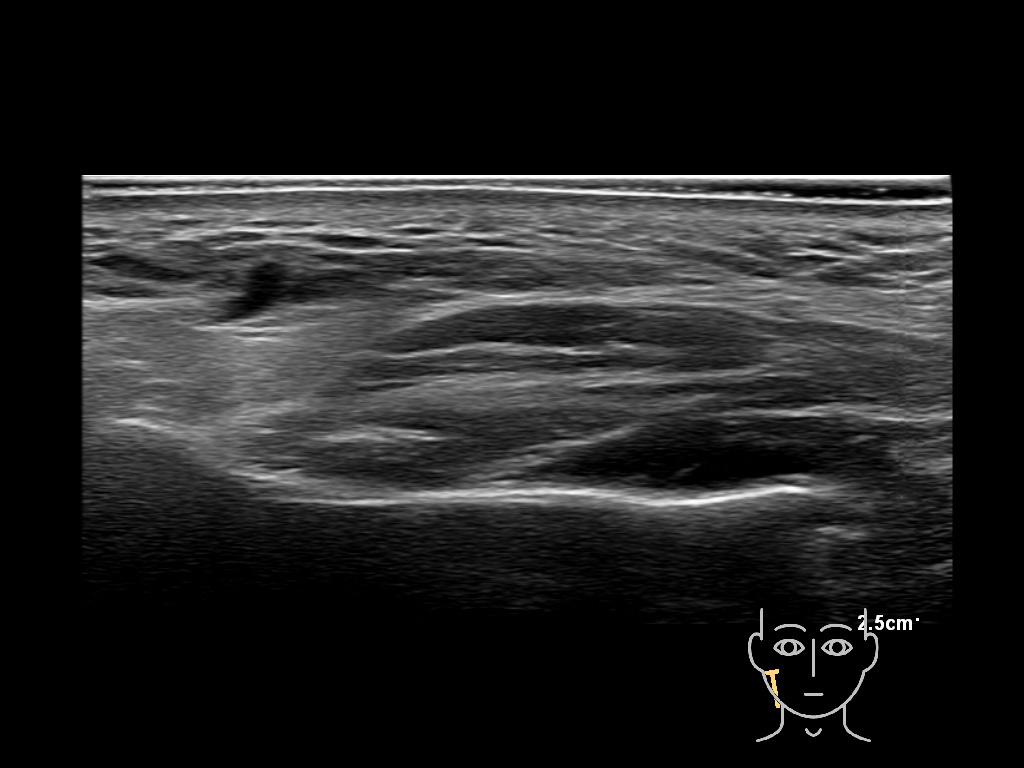

Filler injections in the parotid gland may go unnoticed, however, inflammatory reactions and abscesses may occur. Hypervascularity can be seen with color doppler. Filler deposits are supposed to be injected into the superficial fatty layer . The space to inject into this layer may be limited. Routinely we measure a width of 2-4 millimeters with sometimes subcutaneous layers being less than one millimeter thick.

Study the first image to recognize the different layers. If you are sure about the layers, swipe to the second image to view the answer (if applicable).